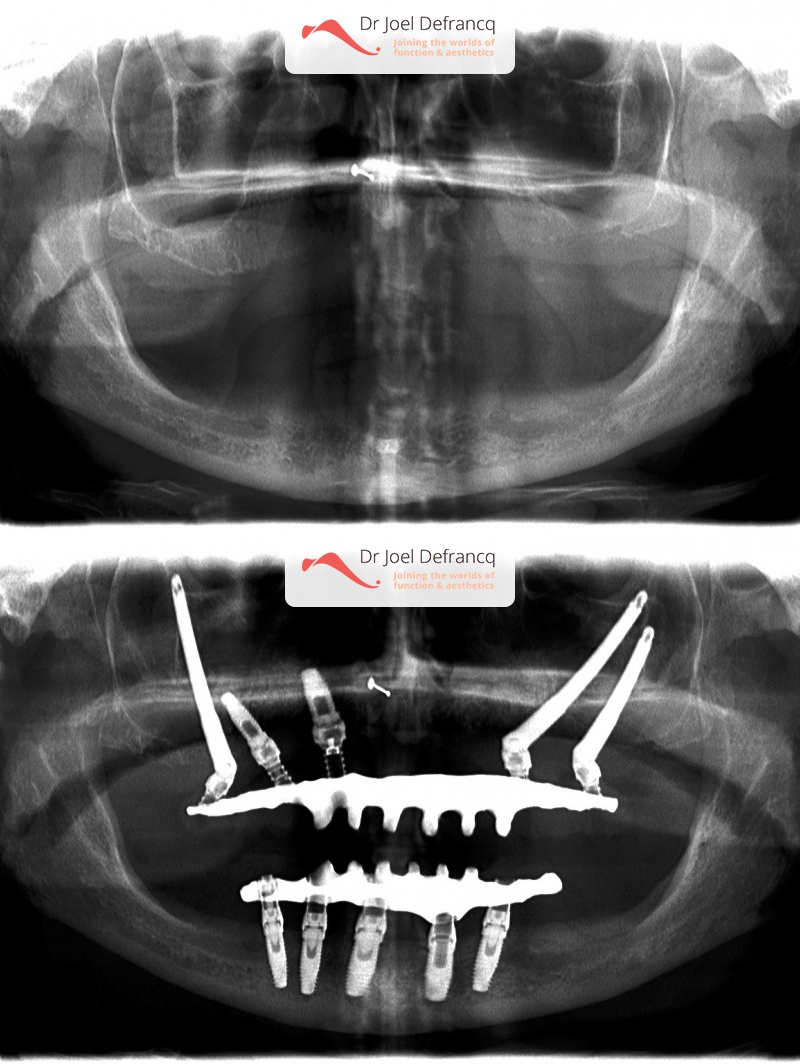

Behandeling tandheelkundige implantaten

- Vaste tanden op implantaten (bovenkaak)

- Vaste tanden op implantaten (onderkaak)

- Zygoma implantaten